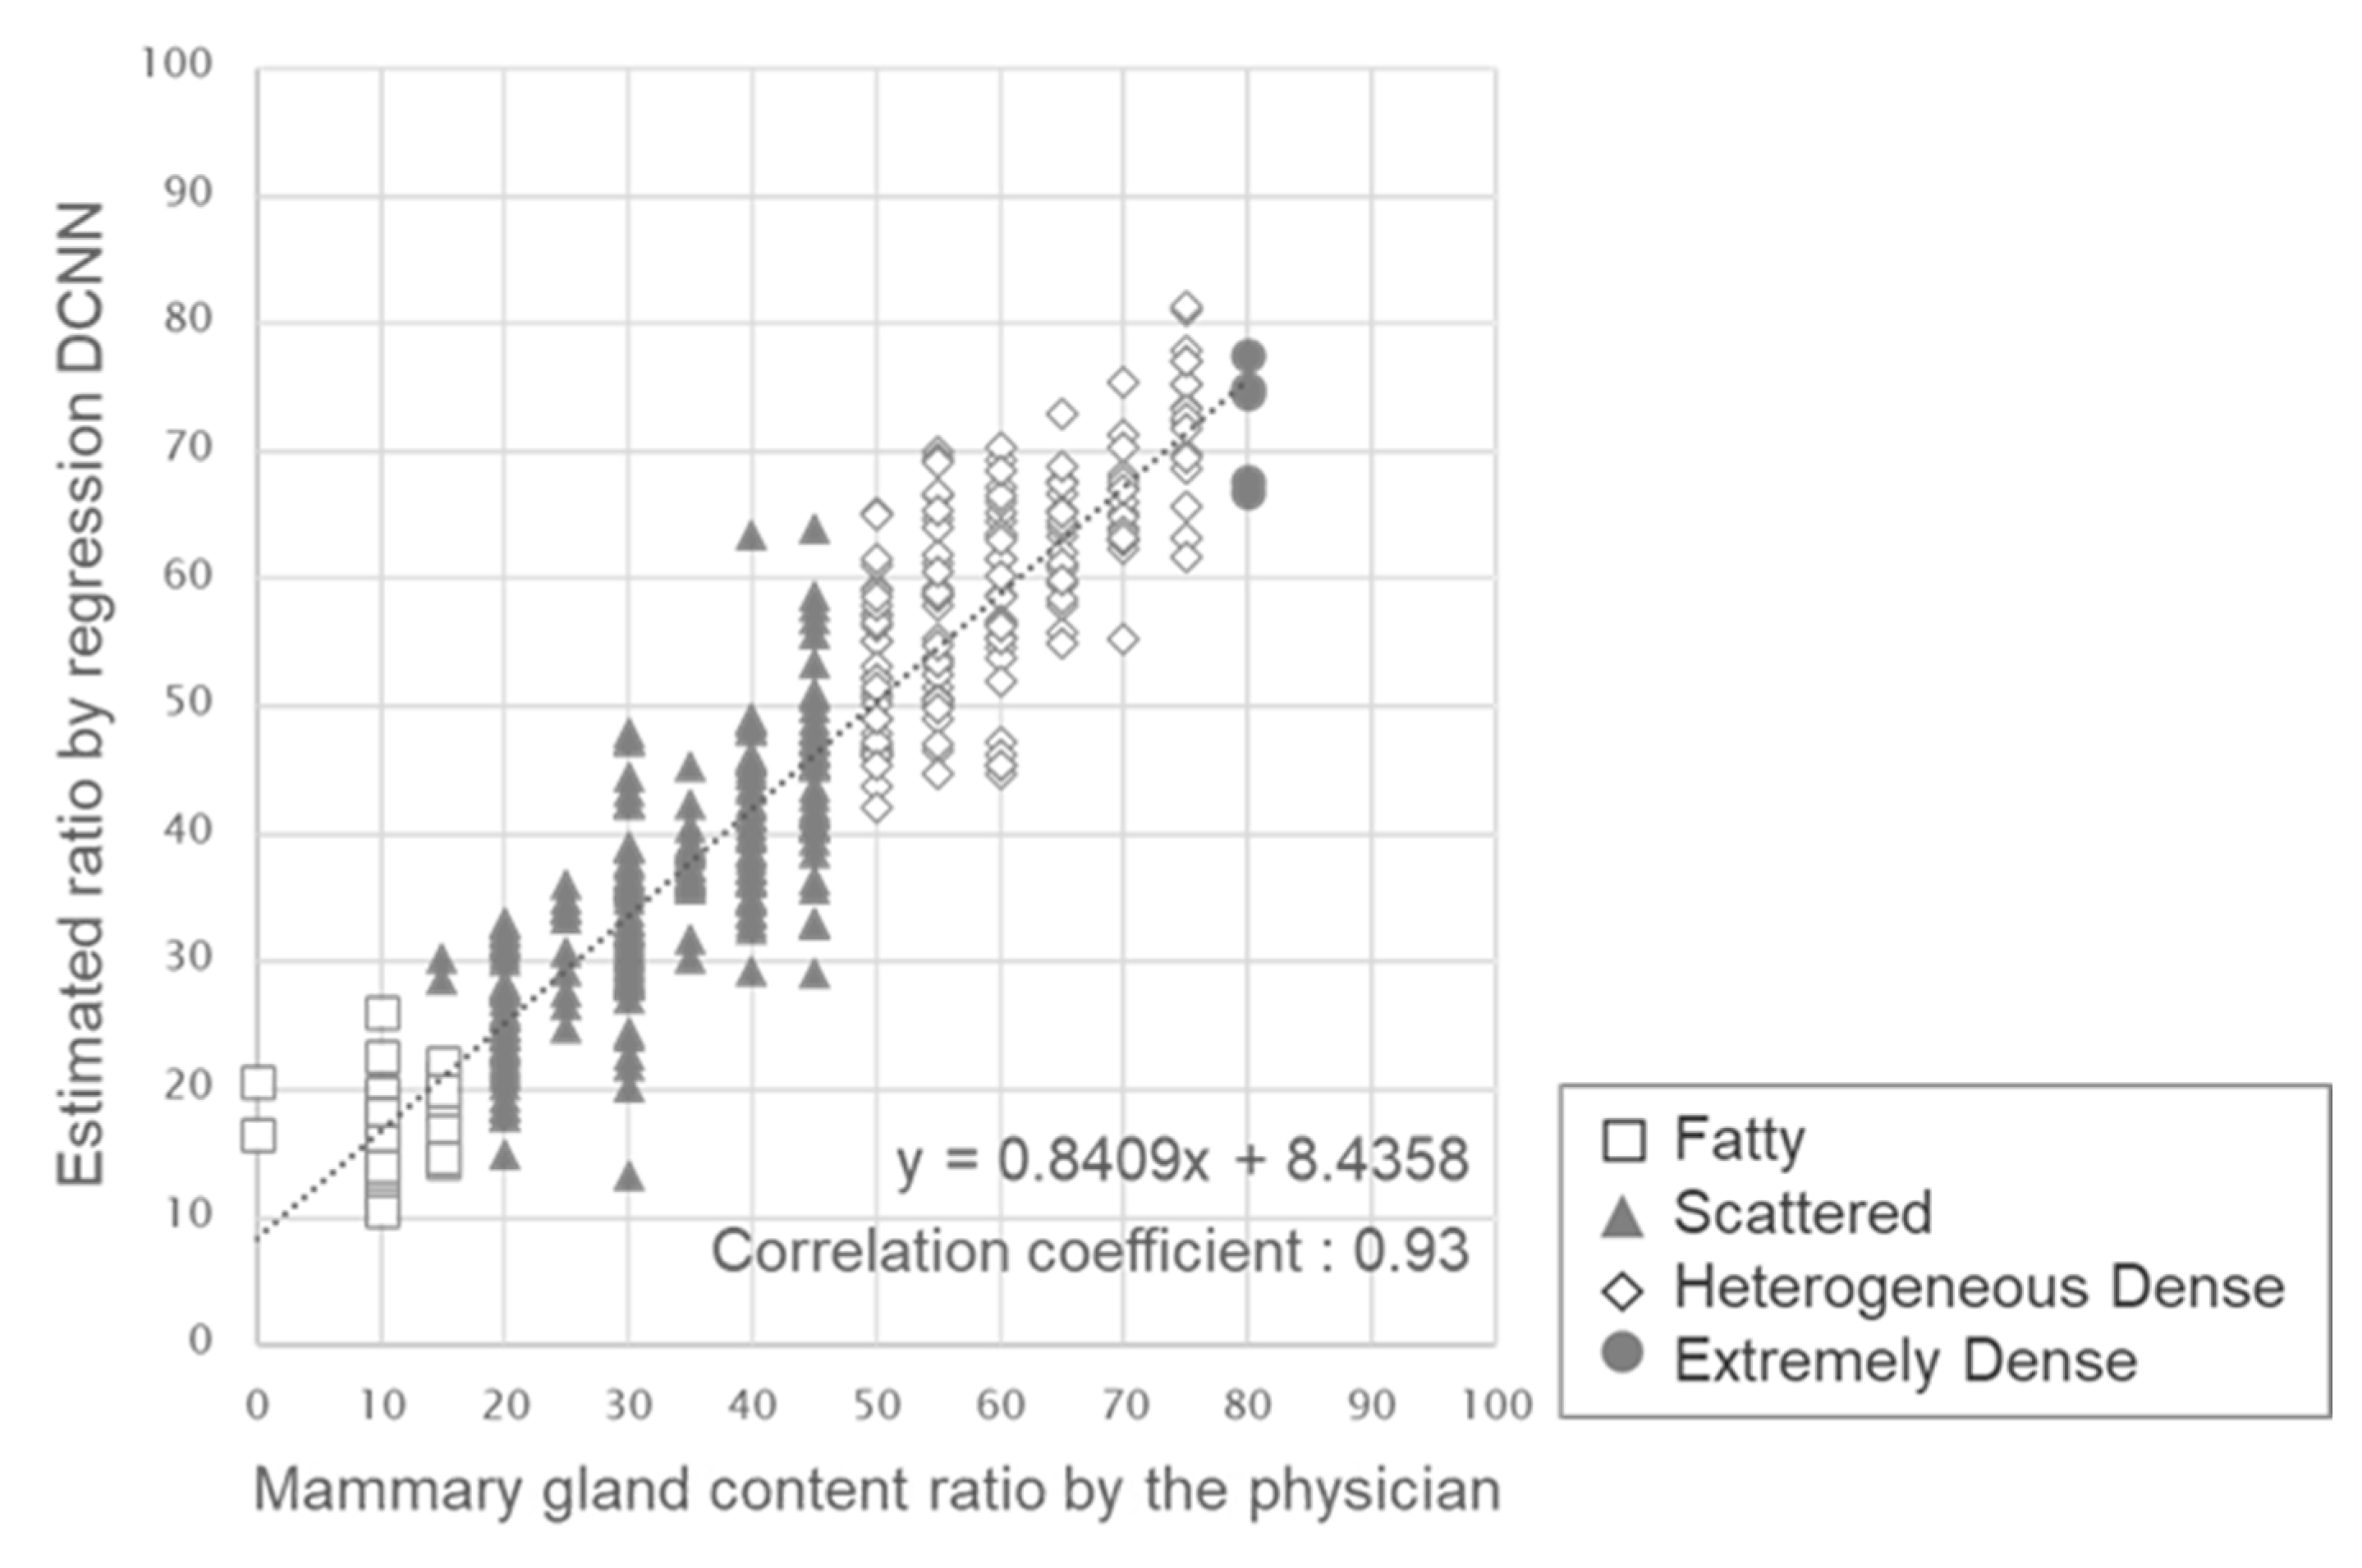

3. Results

4. Discussion